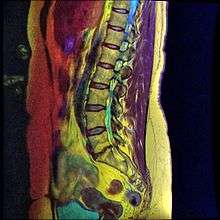

A retrolisthesis is a posterior displacement of one vertebral body with respect to the adjacent vertebrae to a degree less than a luxation (dislocation). Clinically speaking, retrolisthesis is the opposite of spondylolisthesis (anterior displacement of one vertebral body on the subjacent vertebral body), and is also called retrospondylolisthesis.[1] Retrolistheses are most easily diagnosed on lateral x-ray views of the spine. Views, where care has been taken to expose for a true lateral view without any rotation, offer the best diagnostic quality.

Retrolistheses are found most prominently in the cervical spine and lumbar region but can also be seen in the thoracic area.